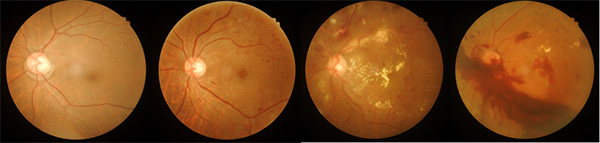

糖尿病视网膜病变早期表现:糖尿病人长时间血液内的高血糖水平,导致视网膜血管出现损害,血管内物质容易溢出,出现视网膜出血及渗出等,如这个阶段不影响视力,患者往往没有自觉症状,对生活及工作影响不大。处于这个阶段的患者眼部往往不需要治疗,需要患者严格控制血糖水平以及定期眼科门诊复查。无视网膜病变到有视网膜病变,是一个量变到质变的过程,一旦出现眼底病变,糖尿病患者需要更好地控制血糖,以延缓糖尿病视网膜病变进展,避免有生之年的视力进展到影响生活的地步。

糖尿病视网膜病变晚期表现:随着糖尿病病程延长,视网膜病变进展到视网膜血管大量闭塞,导致视网膜缺血缺氧,进而形成管壁不完整的新生血管,新生血管容易造成反复视网膜前出血、玻璃体出血,进而导致视网膜增殖膜形成、牵拉视网膜脱离等,这也是糖尿病视网膜病变致盲的常见原因。也许有个体差异使然,也有患者即使血糖控制得很好,病情依然进展很快。冰冻三尺非一日之寒,进入到这个阶段,就需要进行眼部治疗干预了,需要眼底激光或者手术治疗。

糖尿病视网膜病变进展